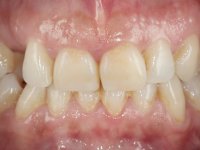

Female patient, 43 years old, non-smoker. Showed an edentulous space in the upper right canine area, resulting from tooth 1.3 impaction. The space had a mesio-distal diameter reduced to the normal size of the upper canine. This is consistent with the presence in the arch of the deciduous canine up to two years ago). Orthopantomography allows clearly view of tooth 1.3 impaction.The patient has a thick gingival phenotype and tolerable oral hygiene.

The proposed treatment results from the limitations imposed by the patient, who refused an orthodontical pull of the canine into the edntulous space, and was unwilling to extract the impacted canine and place an implant in the zone of 1.3. Thus, the confection of a Maryland Bridge was proposed, with a Zr infrastructure and two retainers. The mesial retainer would be bonded to the palatal face of the tooth 1.2 and the distal retainer was to be bonded to the palatal wall of tooth 1.4.